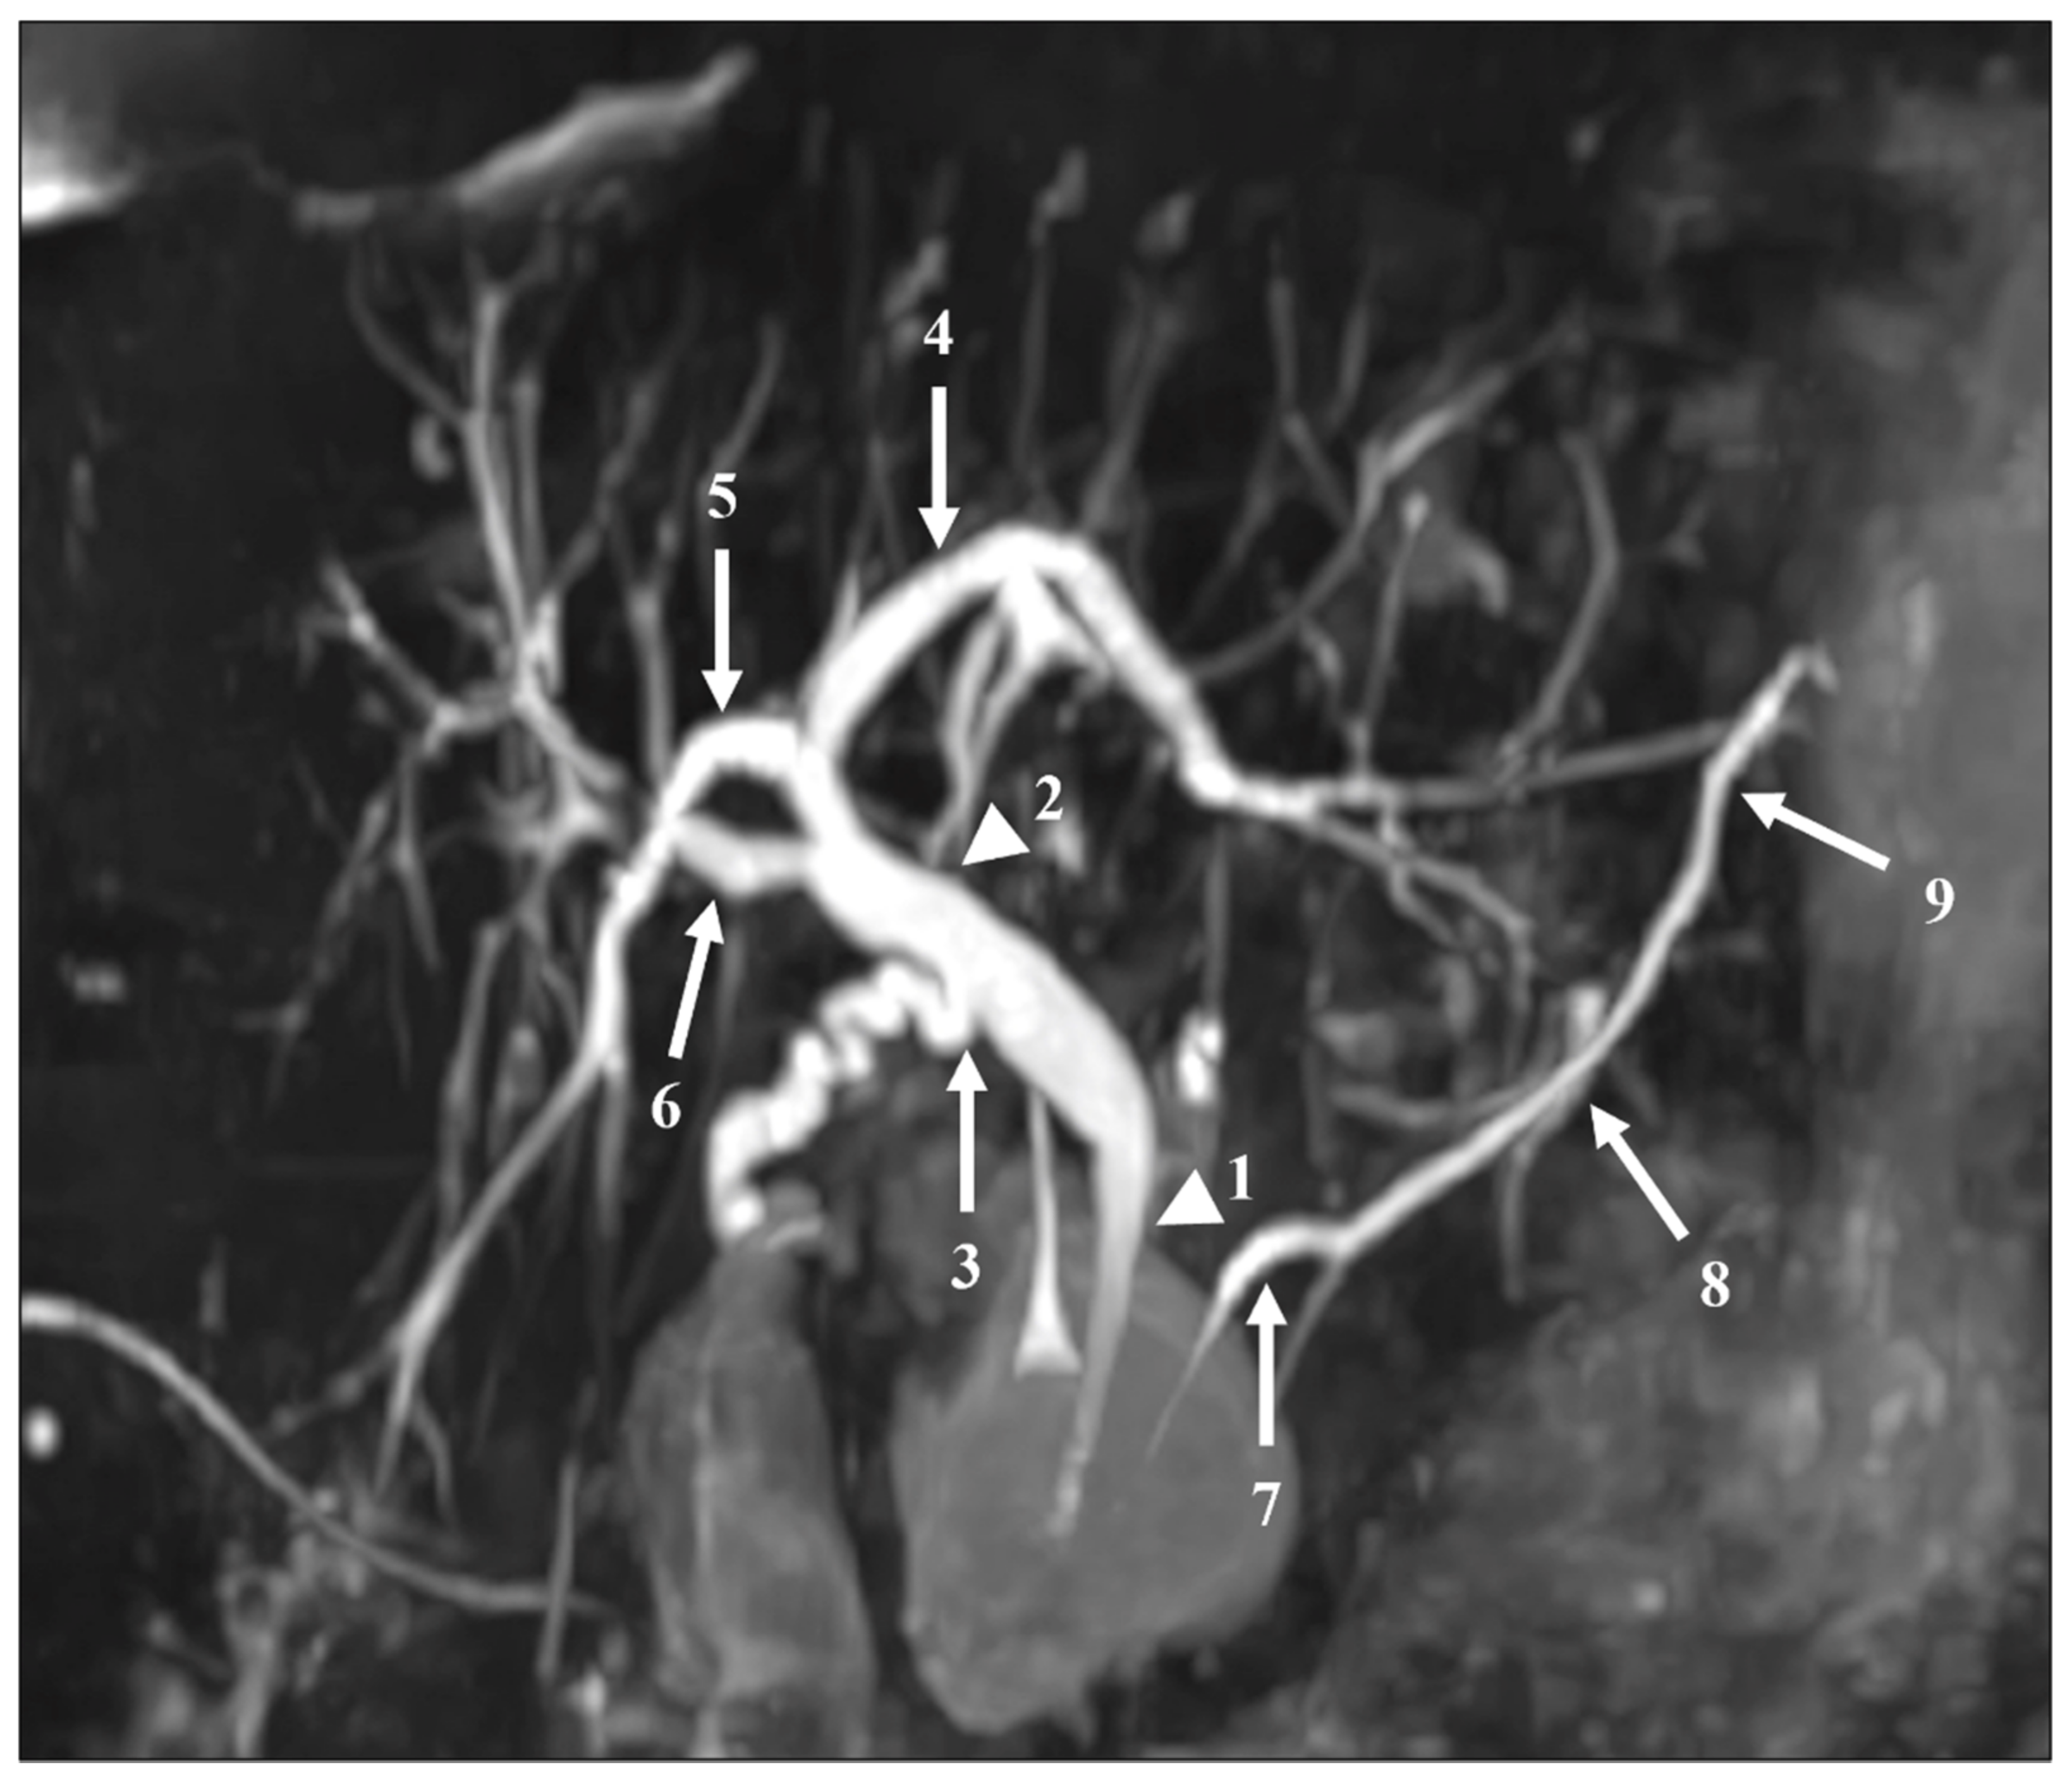

The readers also assessed the visualization of 12 segments of the pancreatic and bile ducts: the proximal and distal parts of the CBD; the confluence of the cystic duct and CBD; the proximal, central, and distal parts of the MPD; the intrahepatic bile ducts (IHBDs) to their primary branches (right and left IHBDs) and secondary branches (right anterior and posterior sectoral ducts and left medial and lateral branches). Each of these 12 segments were evaluated using a five-point Likert scale, with higher scores indicating better duct visualization (Table 2). Figure 2 shows these segments on an MIP reconstruction of a CS-BH-MRCP image.

Figure 2.

The segments of the pancreatic and bile ducts on a MIP reconstruction image acquired with the CS-BH-MRCP sequence for qualitative image quality analysis. Numbers represent the main pancreatic duct (MPD) and bile ducts: (1) distal common bile duct (CBD), (2) proximal CBD, (3) cystic duct confluence, (4) left primary intrahepatic bile duct (IBD), (5) right posterior sectoral IBD, (6) right anterior sectoral IBD, (7) distal MPD, (8) central MPD, (9) proximal MPD. Left medial and left lateral ducts are not represented on this figure. Note that no right primary IBD duct was present in this patient.